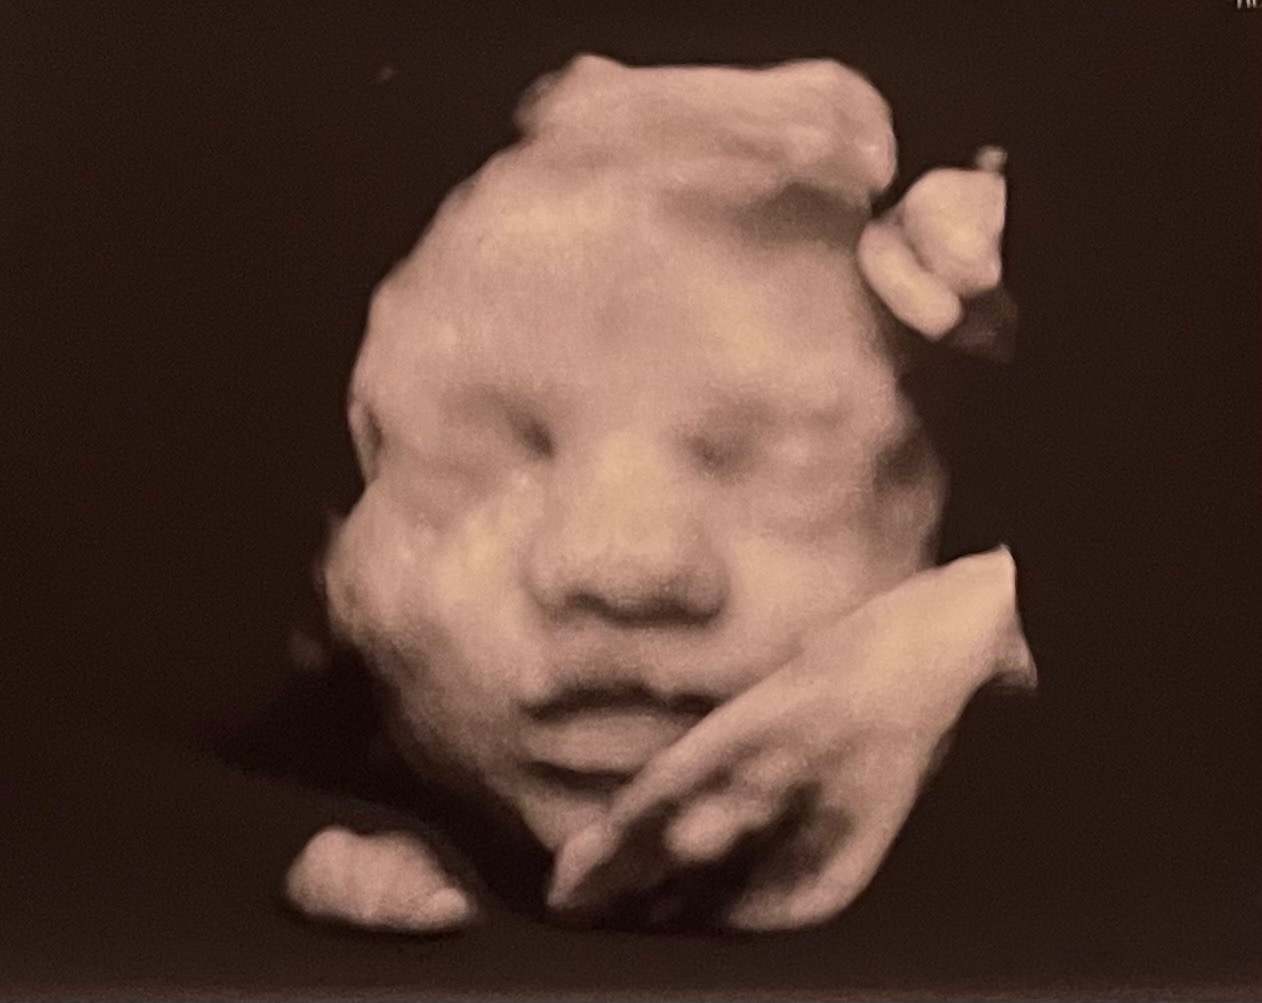

Hi, I’m Jack, and my amazing wife Alicia is now 31 weeks pregnant with our daughter, Sophia Grace. What started as a joyful ultrasound visit, so Alicia’s mom (visiting from California) could see her grandbaby, turned into an unexpected diagnosis at 27 weeks: duodenal atresia, a blockage in Sophia’s small intestine (the “double bubble” sign on MRI).

The great news? Our detailed fetal MRI at Cincinnati Children’s confirmed everything else is perfect; heart, lungs, brain, eyes, spleen, limbs, and strong growth. Genetic testing came back low risk for Down syndrome and other conditions. Sophia is a fighter, and we’re so grateful.

We’ll share updates: scans, the big move, delivery day, surgery, and Sophia’s first smiles. God has carried us every step, your prayers and shares mean the world.